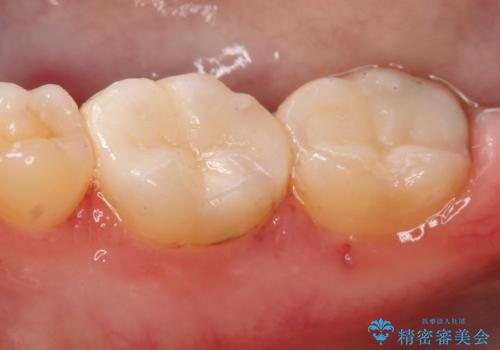

- 右下6・7番の虫歯治療を主訴に来院された患者様です。

精度が高く見た目が良いものを希望されたので、切削量・形態を考慮しセラミックインレーでの治療を計画しました。

奥歯でも下の歯の場合は審美性の高いセラミックを選択される患者様が多いです。